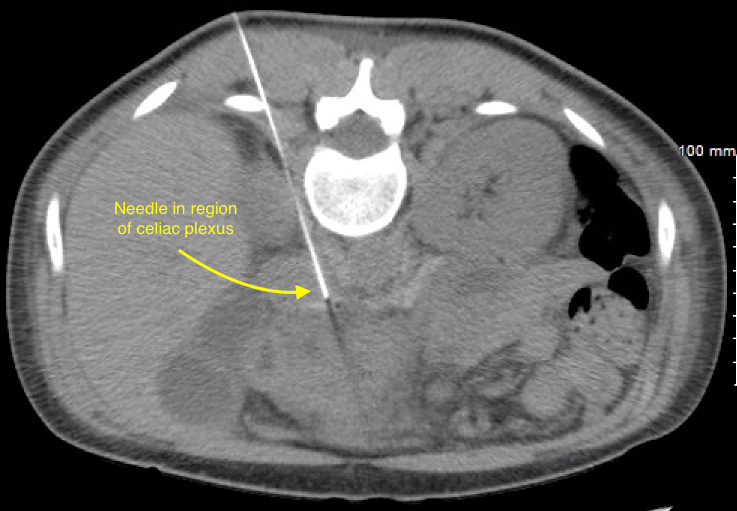

Celiac Plexus Block for Abdominal Pain Explained (602) 5076550 YouTube. The celiac plexus is comprised of three pairs of ganglia:. Change to a lateral view;

Fluoroscopic Guided Celiac Plexus/Splanchnic Nerve Block Technique and Overview The from theprocedureguide.com